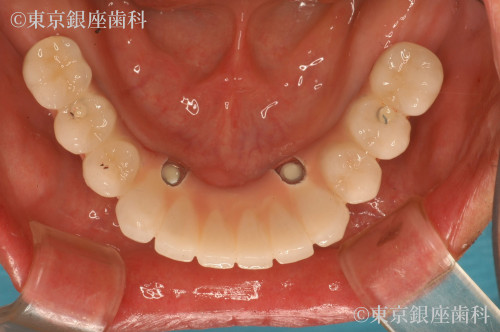

施術内容 インプラント

ワンデイインプラントで審美を回復

上部は審美治療を行い、下部はワンデイインプラントを行った